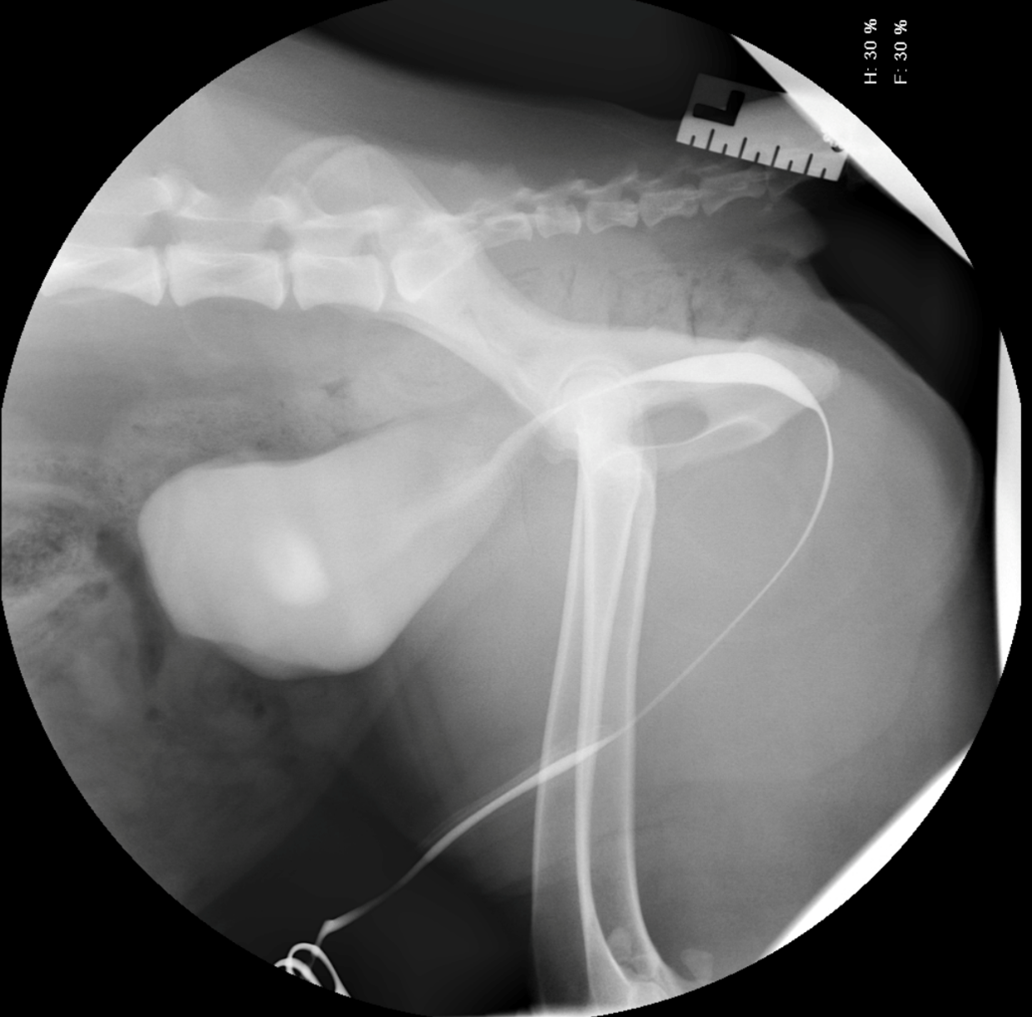

A five-year-old neutered male Shih Tzu presented with a one-month history of haematuria, non-responsive to non-steroidal anti-inflammatory and antibiotic therapy. Physical and external urogenital examinations were unremarkable.

Haematology, biochemistry and urinalysis were unremarkable. However, abdominal radiography revealed a moderately sized, round, smoothly marginated mineral opacity in the urinary bladder on abdominal radiography, consistent with a cystolith (Figure 4). This was removed via minimally invasive cystotomy, and analysis confirmed this to be calcium oxalate.